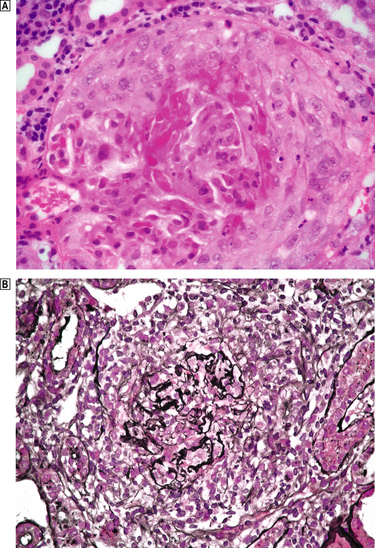

Histologically, the characteristic lesion is a focal and segmental glomerulonephritis. With increasing severity, segmental necrosis with fibrin deposition, and a florid crescentic glomerulonephritis occurs (Fig. 21.5).

image

Fig. 21.5 Anti-glomerular basement membrane disease. The glomerular injury in this case is due to anti-glomerular basement membrane antibody. image The resulting damage causes obliteration of the Bowman’s space by macrophages, inflammatory cells and epithelial cells forming a crescent. image Immunofluorescence reveals linear deposition of immunoglobulin on the glomerular basement membrane.